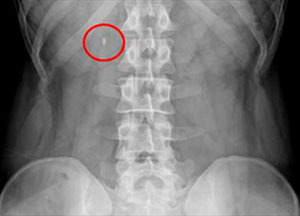

요로결석은 콩팥·요관·방광 등에 소변 속 물질이 뭉쳐 돌처럼 쌓이는 질환으로 소변에 결석을 만드는 성분이 많아질 때 생기기 쉬운데, 활동량이 늘고 기온이 올라가기 시작해 갑자기 몸속 수분이 부족해지는 봄에는 소변량이 줄고 농도가 높아져 결석이 잘 생기는 환경이 만들어진다.

요로결석의 대표 증상은 갑자기 한쪽 옆구리나 허리에 찾아오는 심한 통증이다. 통증은 아랫배나 사타구니 방향으로 내려가기도 하며, 소변에 피가 섞여 나오거나 구토 증상이 나타날 수도 있다.

이러한 증상을 방치할 경우 결석이 요로감염, 패혈증까지 유발할 수 있기 때문에 예방과 조기 치료가 필요하다. 또한 통증이 없거나 일시적으로 사라져도 결석은 남아있을 수 있어 진료가 권장된다.

이미 요로결석이 생겼다면 병원을 찾아 적절한 치료를 받아야 한다. 박 교수는 "결석의 크기가 작다면 수분 섭취·약물치료를 통한 자연 배출을, 크거나 위치가 좋지 않다면 충격파·내시경 쇄석 치료를 고려한다"고 설명했다.